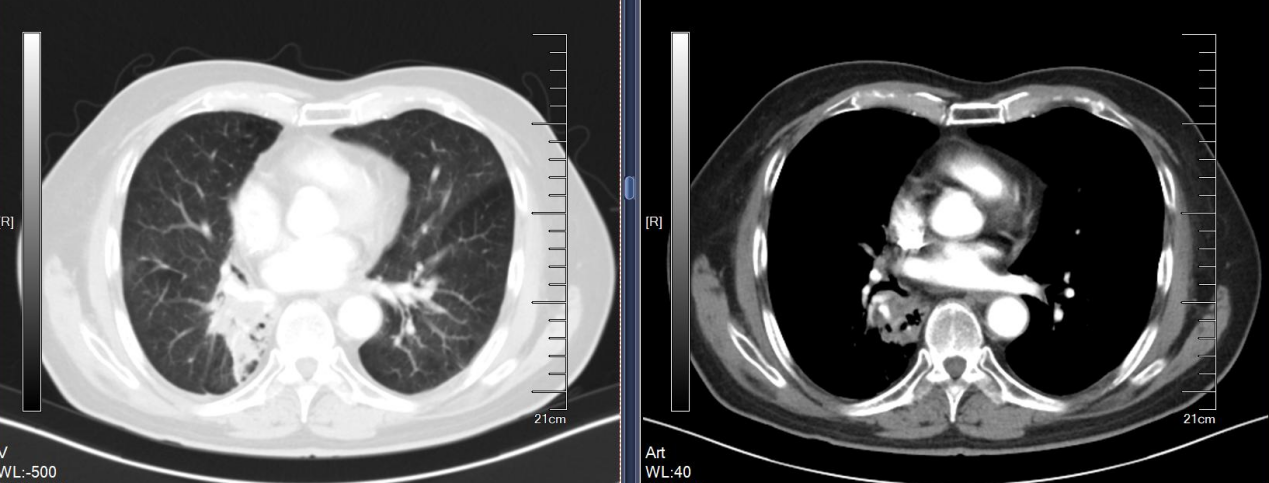

放疗:患者入院后完善相关检查检验,排除禁忌于2024年8月5日开始行放疗,靶区:右肺下叶病灶,剂量:50Gy/25Fx,于2024年9月6日完成放疗,放疗同期行白蛋白紫杉醇+卡铂治疗5周期,并予甘氨双唑钠增敏,期间出现化疗后骨髓抑制,经治疗后好转。治疗后患者咳嗽较前好转。

疗效评估:

放疗后1月:2024年10月胸部CT:右肺下叶膨胀不全,右肺下叶肺门旁团块影,结合病史考虑肿瘤治疗后改变;2. 右肺上叶后段、左肺下叶背段慢性炎症伴局部支扩。

图4. 放疗后1月

放疗后3月:2024年12月11日复查胸部CT:1. 右肺下叶肺门旁团块影,右肺下叶部分肺不张,较前(2024-10-16)病变范围大致相仿,结合病史考虑肿瘤治疗后改变;右肺炎症,较前新发,治疗后复查。2. 慢性支气管炎、肺气肿。左肺下叶条索影伴轻度支气管扩张。3. 附见:肝内小囊肿可能。